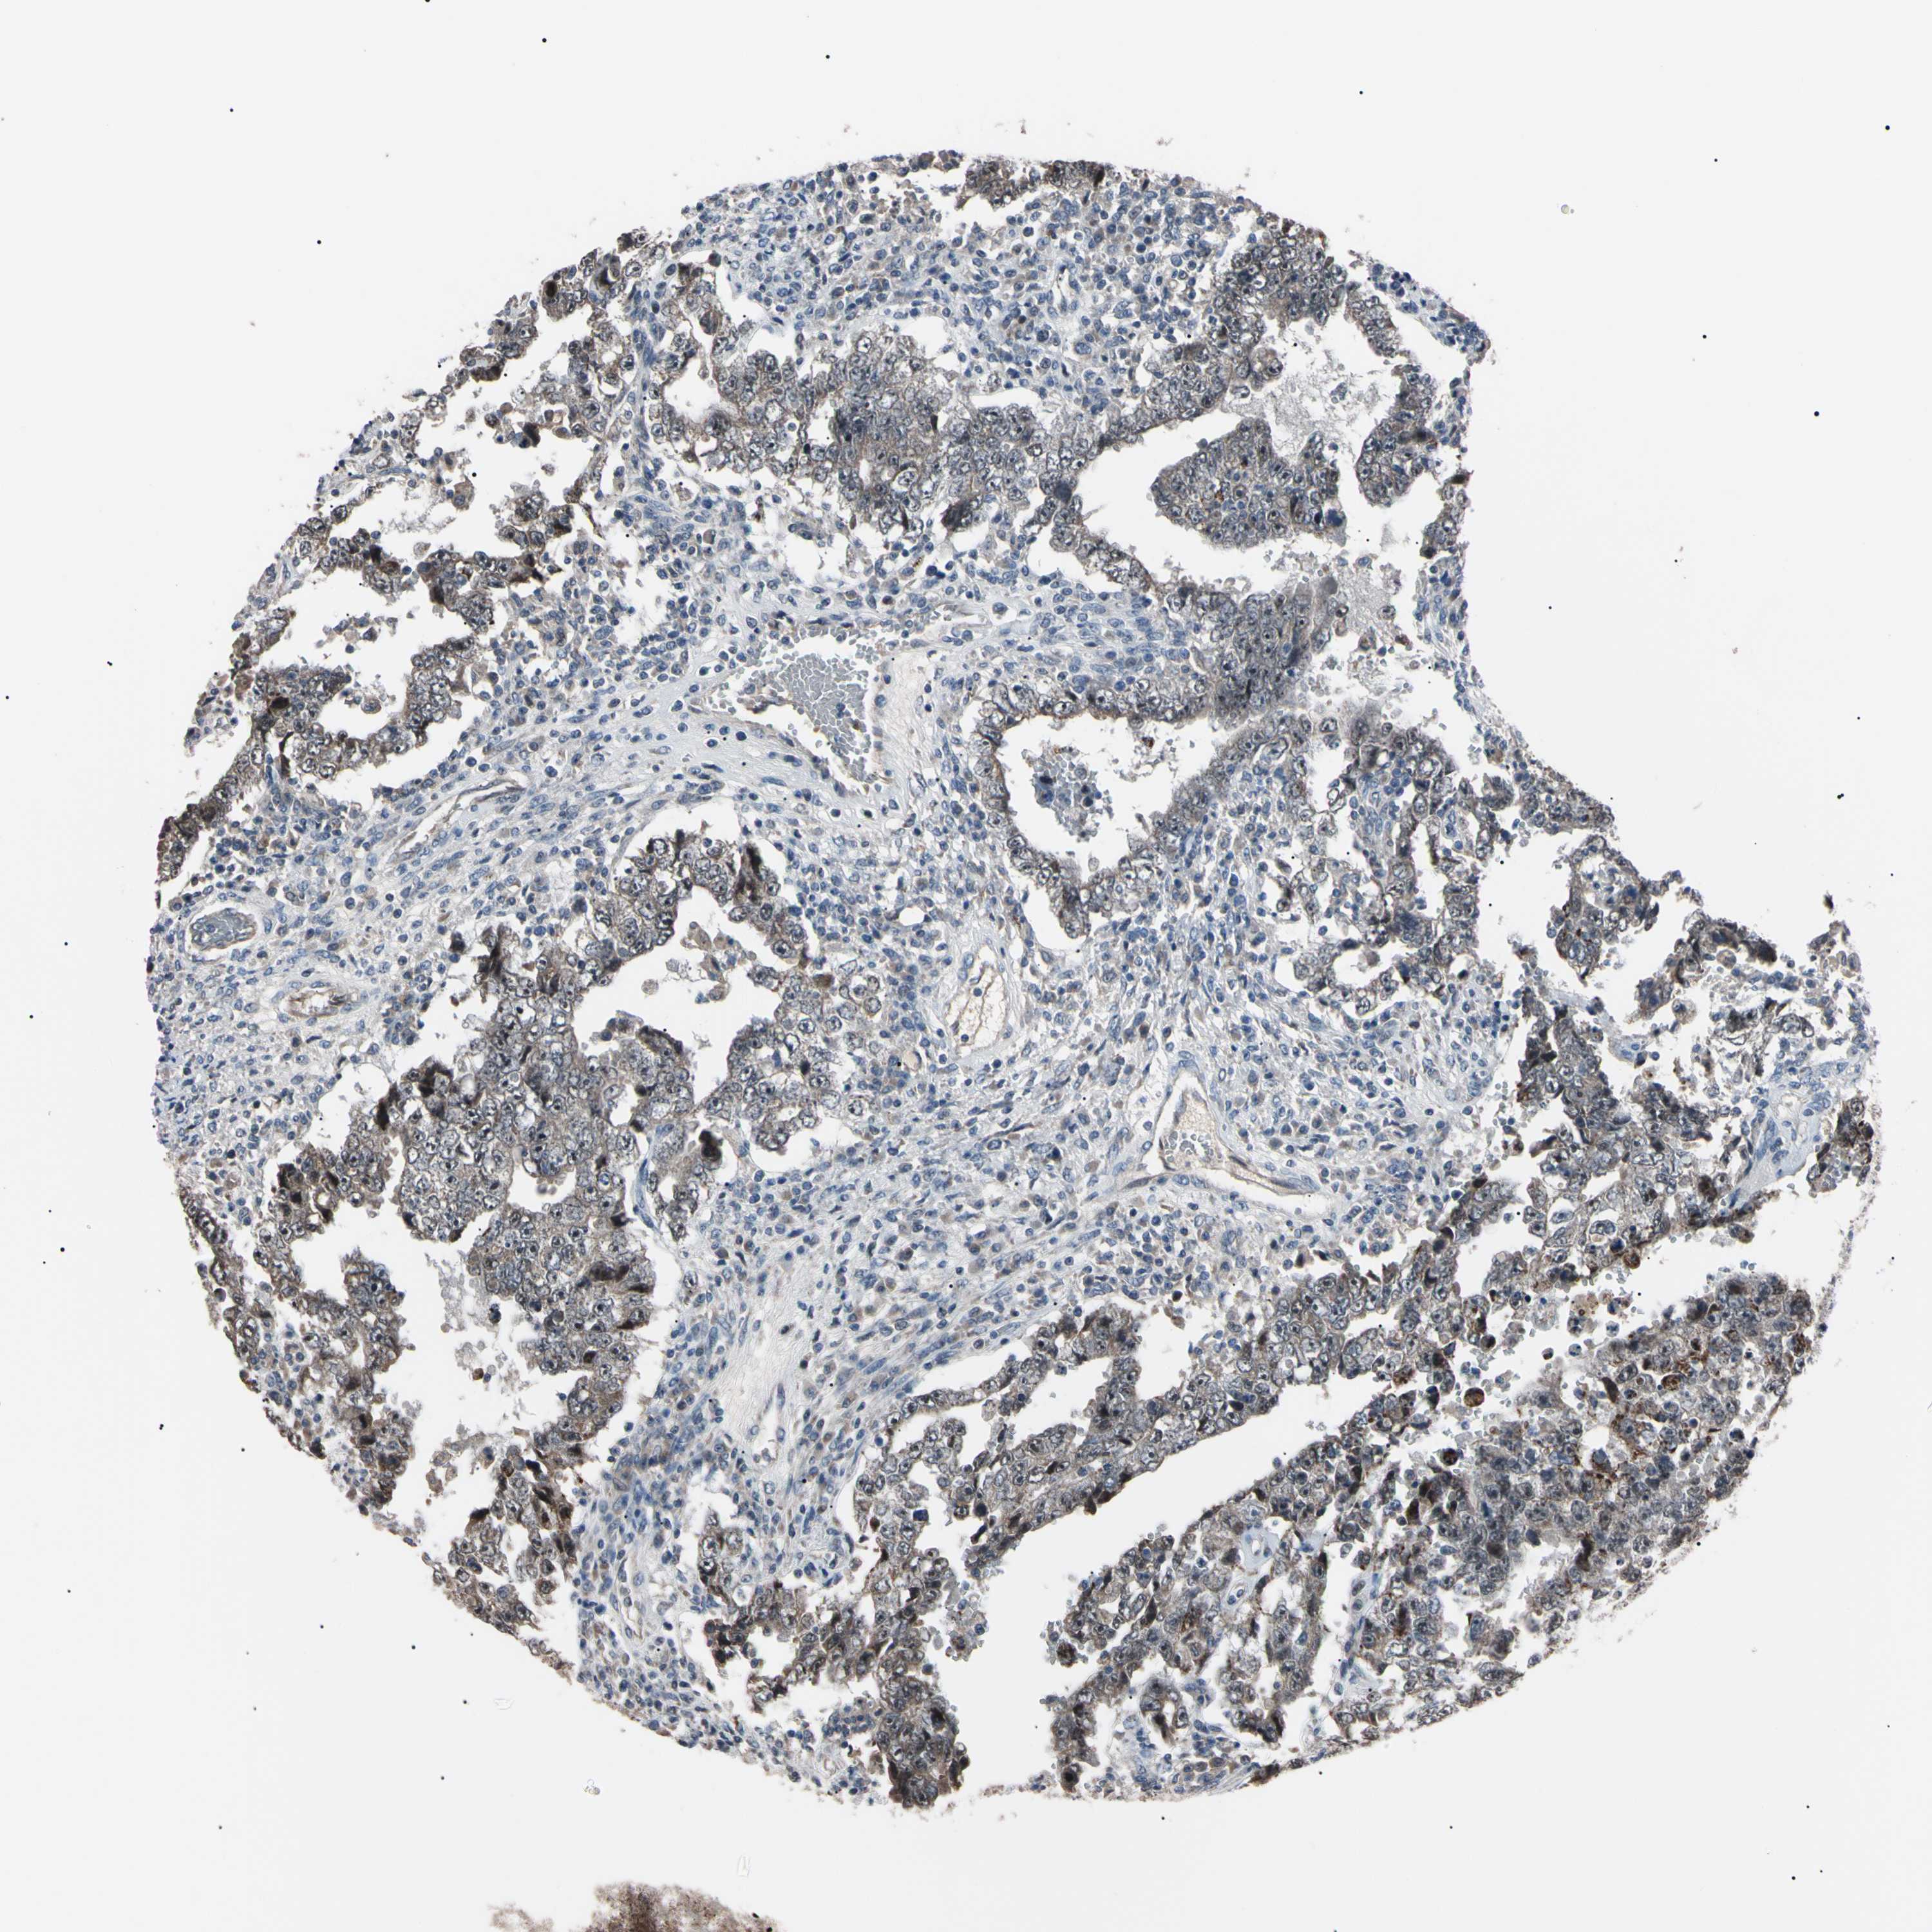

TESTIS CANCER - Protein expressioni

A mouse-over function shows sample information and annotation data. Click on an image to view it in a full screen mode. Samples can be filtered based on level of antibody staining by selecting one or several of the following categories: high, medium, low and not detected. The assay and annotation is described here.

Note that samples used for immunohistochemistry by the Human Protein Atlas do not correspond to samples in the TCGA dataset.

Antibody stainingi

Antibody staining in the annotated cell types in the current human tissue is reported as not detected, low, medium, or high, based on conventional immunohistochemistry profiling in selected tissues. This score is based on the combination of the staining intensity and fraction of stained cells.

Each image is clickable and will lead to virtual microscopy that enables deeper exploration of all samples and also displays staining intensity scores, fraction scores and subcellular localization as well as patient and tissue information for each sample.

Antibody HPA008052

Antibody CAB010277

Carcinoma, Embryonal, NOS

Seminoma, NOS